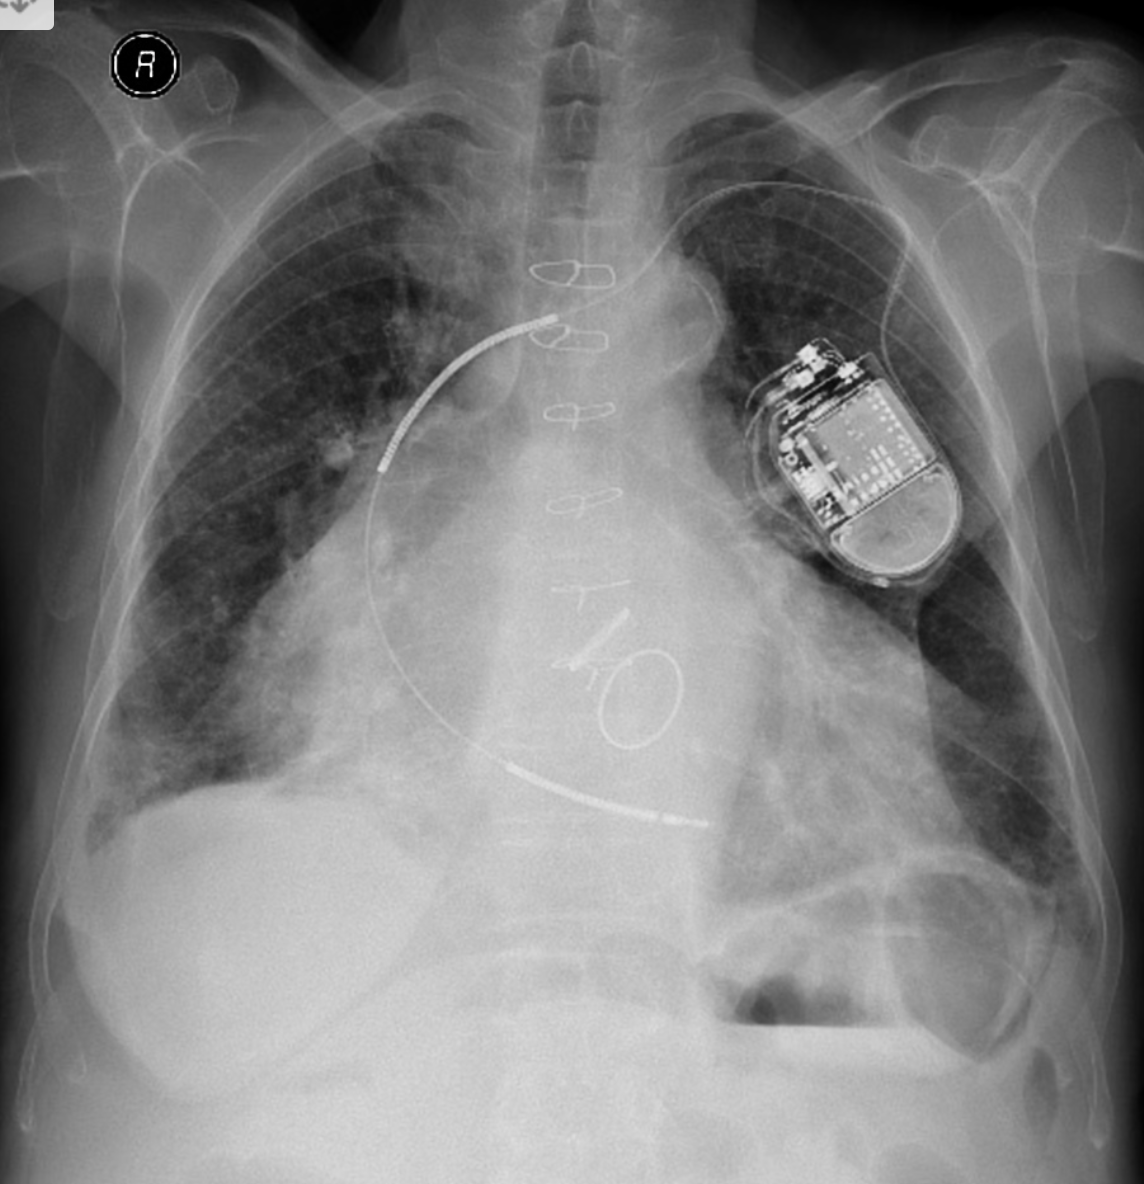

-Dual chamber ICD with RA lead dislodgment